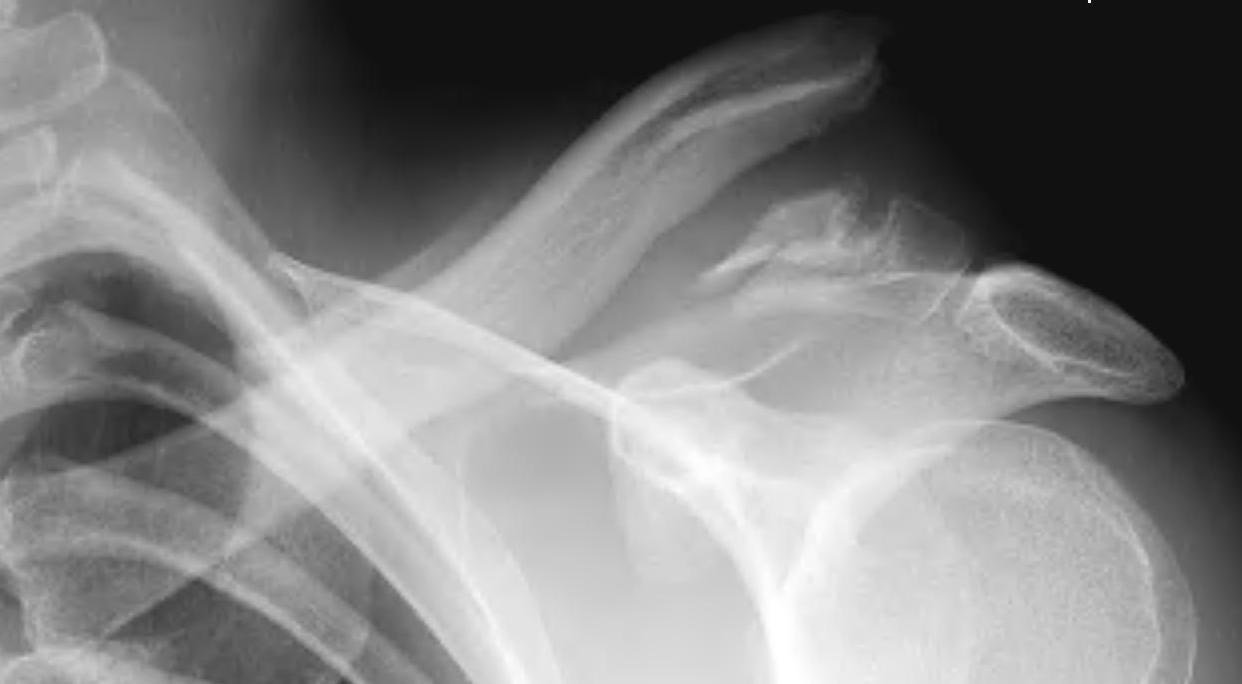

Neer Classification

Fracture lateral to the CC ligaments Non displaced

Fracture medial to the CC ligaments CCL ligaments attached to lateral fragment Medial fragment displaced superiorly |

Between conoid and trapezoid Conoid disrupted Trapezoid remains attached to the lateral fragment |

Lateral to CC ligaments Intra-articular extension Stable |

Periosteal sleeve disruption Pediatric Medial fragment displaced |

Comminuted Type II Medial fragment displaced |

Type I

Type II

Type V